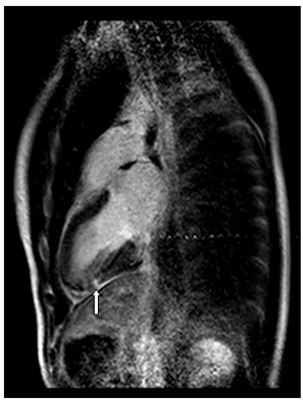

Testing was done for collagen vascular diseases, as well as a Mantoux test, all of which were negative. The patient’s ESR was also within the normal range, consistent with the focal nature of his inflammatory process that did not mount a systemic response. On the third day of hospital admission, the patient’s symptoms had resolved, with normalization of his cardiac enzymes. He was discharged without any new medications, and followed up with a repeat cardiac MRI in two months that showed no abnormalities (Figure 2b). The patient reported no recurrence of his chest pain.

Figure 2B Repeat cardiac MRI in two months that showed no abnormalities.